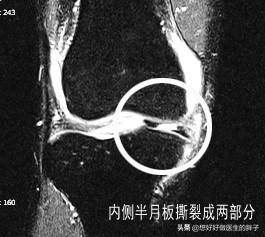

第三,半月板影像。接下来提示外侧半月板后角斑片状高信号影,达关节面边缘;前角内见线性高信号影(未提及达关节面说明没有)。这里说的半月板后角达关节面边缘,就说明外侧半月板是III°撕裂,核磁影像一般是这样的:

或者是这样的:

大家可以看到半月板已经完全有一部分离家出走,损伤肯定突破了其上下表面,并且导致了关节内的大量积液。而镜下很可能是这样子的: